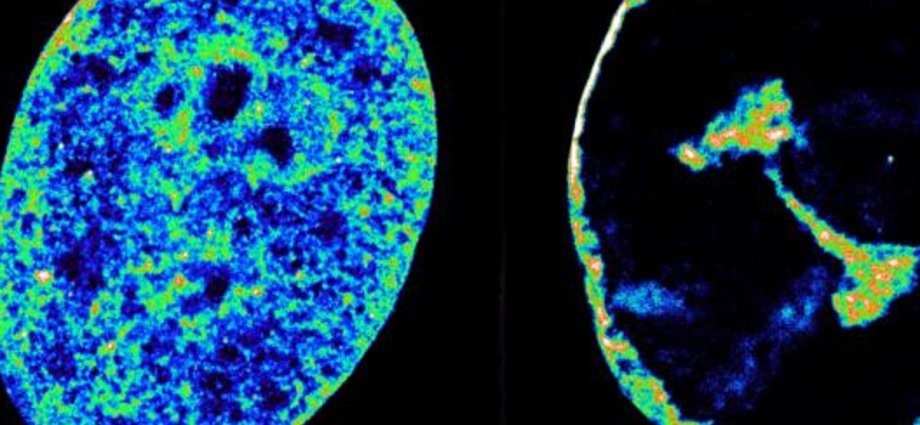

In the study, scientists used super-resolution microscopy to peer into ultra small cell structures just 20 nanometres wide, which is around 3,500 times thinner than a strand of hair.

They combined this with another technique that reveals which bits of DNA are touching inside the nucleus.

These techniques showed that the herpes virus’ hostile takeover begins within the first hour, with the virus hijacking a key human enzyme – RNA-polymerase II – to synthesise its own proteins.

Just three hours after infection, the virus causes a sizeable fraction of molecules involved in human DNA replication to abandon the cell nucleus and enter viral replication compartments.

The wholesale theft causes a collapse of any activity across the host genome, which then gets crushed into a dense shell just 30 per cent of its original volume.